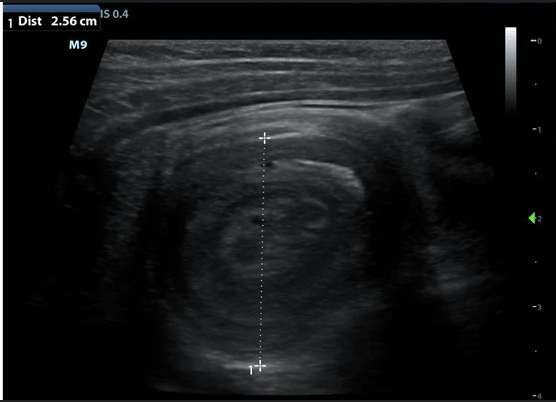

The name of this abdominal US finding.

What is intussussception?